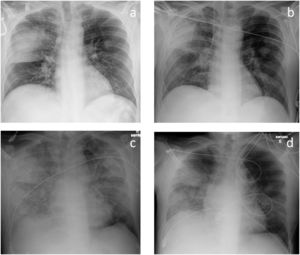

We present the case of a 48-years-old Caucasian male, with a personal history of chronic alcohol abuse and current smoker (20 UMA). No history of respiratory diseases was known. The patient was admitted to the emergency department with a three-day history of fever, dyspnea and cough with mucopurulent sputum. During physical examination, he was conscious but disoriented, tachycardic and tachypneic, with a hypotensive profile. Pulmonary auscultation revealed a decrease in the breath sounds over the right middle hemithorax. Arterial blood gas analysis revealed partial respiratory failure and hyperlactatemia (lactate of 7.7 mmol/L). Laboratory tests showed thrombocytopenia, acute kidney injury and liver failure. Urinary antigen was positive for Streptococcus pneumonia. Chest radiography showed an opacification in the middle level of the right hemithorax (Fig. 1) and computed tomography of the chest revealed a consolidation in the posterior segment of the right upper lobe.

On the 13th day of hospitalization, he was hemodynamically stable and eupneic with oxygen therapy (FiO2 = 0.36, PaO2/FiO2 = 208, Table 1). Due to acute anemia, two units of erythrocyte concentrate were given to the patient. After completing the transfusion, there was worsening of the hypoxemia (PaO2/FiO2 = 120, Table 1) and pulmonary auscultation revealed disperse rales, especially bibasilar. Chest radiography showed new bilateral pulmonary infiltrates (Fig. 1).